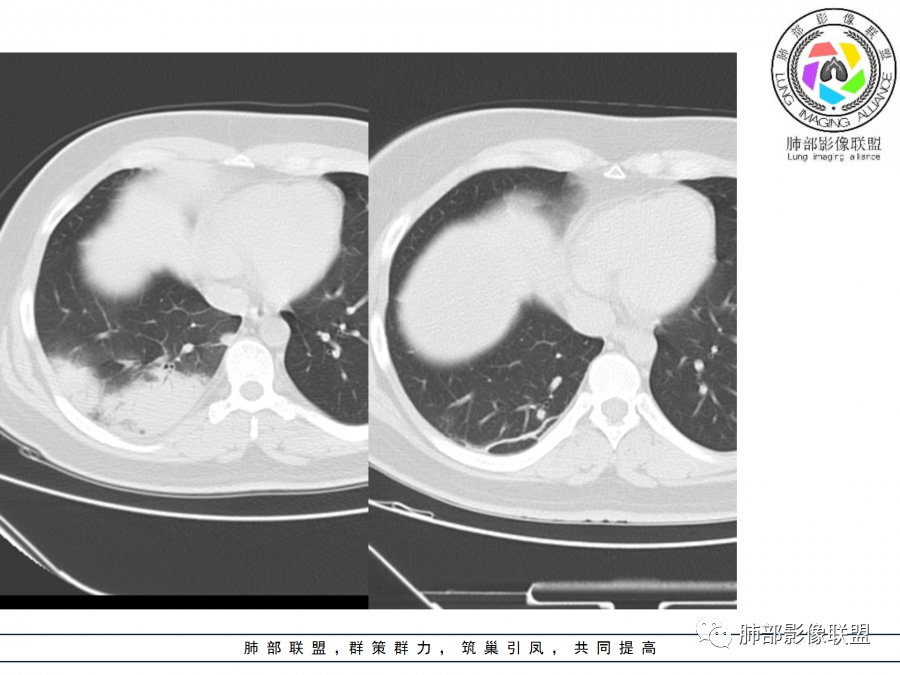

右肺胸膜下实变,病变跨多个叶生长,宽基底与胸膜相连,近端支气管穿行病灶内,并可见片状磨玻璃影,边界清,部分远端小支气管堵塞,支气管略有扩张,周围散发小结节,临床年轻女性,炎性指标高,发热六日,首先考虑感染性病变(肺链,奴卡,隐球,OP)鉴别淋巴瘤。

年轻女性,无明显诱因发热,体温略高,起病较急,有畏寒,右下肺紧贴胸膜下片状实变影,部分融合,外围有结节影,性质比较单一,类似于蘑菇兄弟,病灶周围伴有晕,支气管进入近端扩张远端堵塞,常规考虑感染,肺炎链球菌、隐球菌。

青年女性,发热咳嗽5天,炎症标志物升高。右肺下叶大片实变伴周围GGO,GGO内未见细网格,主体与胸膜平行,似多个病灶融合,实变区内见支气管部分进入,部分支气管受压狭窄,周围可见多发卫星病灶。支持炎性,考虑隐球感染,鉴别op。

年轻女性,急性起病,咳嗽,发热,黄痰,白细胞高,CRP基本正常,基础体健。CT提示右肺下叶实变,宽基底与胸膜相连,长轴平行于胸膜,可见支气管充气征,于病变中央截断,走形自然,胸膜下脂肪间隙可见,倾向于隐球菌,鉴别肺链,军团菌等。

年轻患者,右肺下叶大片状实变影,长轴与胸膜平行,内见含气支气管征,周围磨玻璃晕影。考虑感染性病变,隐球?

病灶长轴与胸膜平行,边缘有晕,病灶融合趋势,支气管进入,走行自如,考虑隐球菌肺炎。

年轻女性,急性发病,咳嗽咳痰五天,炎性指标升高,右肺下叶胸膜下大片实变影,周围见磨玻璃影,边界清晰,长轴与胸膜平行,呈融合趋势,支气管进入走行自然,远端截断,考虑炎性,隐球菌可能。

年轻女性,发热,急性发病,白细胞高,右肺下叶大片实变,长轴与胸膜平行,内见支气管走行,远端截断,周围有晕,晕边界清,考虑感染,隐球可能,鉴别淋巴瘤。

年轻女性,右肺下叶胸膜下多发实变、结节影,宽基底与胸膜相连,边缘模糊不清,实变内见支气管穿行,血象高,考虑感染性病变,大叶性肺炎?隐球?

青年女性,发热咳嗽急性起病,右肺下叶大片状实变密度影,长轴平行于胸膜,边缘模糊可见磨玻璃影及高密度结节影,实变内可见支气管穿行,直达病灶远端,考虑感染性病变,隐球菌可能大。

右肺胸膜下实变,病变跨多个叶生长,相互融合,宽基底与胸膜相连,支气管气象,并可见片状磨玻璃影,边界清,炎性指标高,发热六日,考虑感染病变,链球菌?腺病毒待排。

右肺下叶大片状实变影,长轴平行于胸膜,边缘模糊可见磨玻璃影,支气管进入,部分近端阻塞,考虑感染性病变,隐球菌,鉴别大叶性肺炎。

年轻女性,起病急,白细胞,C反高,存在感染。右下肺大片实变影,支气管充气征,长轴平行胸膜,似多个病灶融合,周围GGO,部分清,部分不清。考虑感染,隐球可能。

青年人,右肺多发团片状阴影,边缘模糊,周围可见磨玻璃影,内部有支气管空气征,考虑感染性病变,隐球菌感染可能。

右肺下叶大片状实变影,从外向内,长轴平行于胸膜,边缘模糊,可见磨玻璃影,支气管进入,远端部分阻塞,考虑感染性病变,隐球菌,鉴别淋巴瘤。

26岁,女性,发热、咳嗽5天。咳少量黄痰,起病急,病程短,白细胞及中性高,血沉及D-二聚体增高。胸部CT:右肺下叶大片实变,长轴沿胸膜分布,宽基底与胸膜接触,边界不清,周围GGO,部分团片影融合,病灶内可见支气管充气征,部分支气管进入病灶后阻塞。考虑:感染性病变,隐球菌?脓毒肺栓塞?鉴别:肺炎型肺Ca。

年轻女性,右肺下叶一大片实变影,似有多个结节影融合,周围有晕,内见支气管充气征,部分支气管进入后截断,病变近胸膜,长轴胸膜平行,考虑炎性,隐球菌首先考虑。

青年女性,影像表现右肺下叶胸膜下大片状实变影,近端见充气支气管征,边缘见片状磨玻璃影,下叶背段尚可见一结节。考虑感染性病变,隐球菌感染可能。

右下肺大片实变影,空气支气管征,边缘GGO,小叶间隔增厚,周围有蘑菇兄弟,基底宽,与胸膜平行,考虑隐球菌感染,鉴别肺炎型肺癌。

晨读:年轻女性,右肺胸膜下实变影,平行于胸膜,边缘磨玻璃影,内见支气管充气征,走形自然,略扩张。考虑感染性改变,隐球,肺链。2月发病,病毒性肺炎要考虑。鉴别淋巴瘤。

晨读:年轻女性,发热咳嗽5天。白细胞计数升高。右肺下叶大片状高密度影,边缘模糊,有实变 GGO,其内见支气管气相、无受压变细,无枯枝表现,其近端支气管无异常,右肺下叶背段见结节状影,定性考虑:炎症,隐球菌感染可能,炎症型肺癌不支持。

右下肺胸膜下大片状高密度影,其长轴与胸膜平行,病灶近端GGO模糊,部分支气管进入后阻断,支持感染性病变,考虑隐球菌